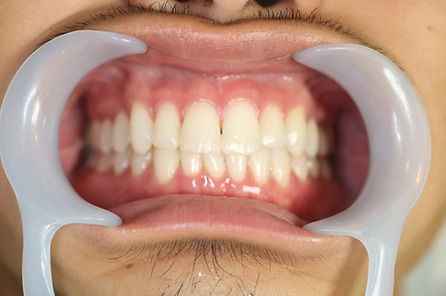

2ホワイトニング【治療例2】

治療前

治療後